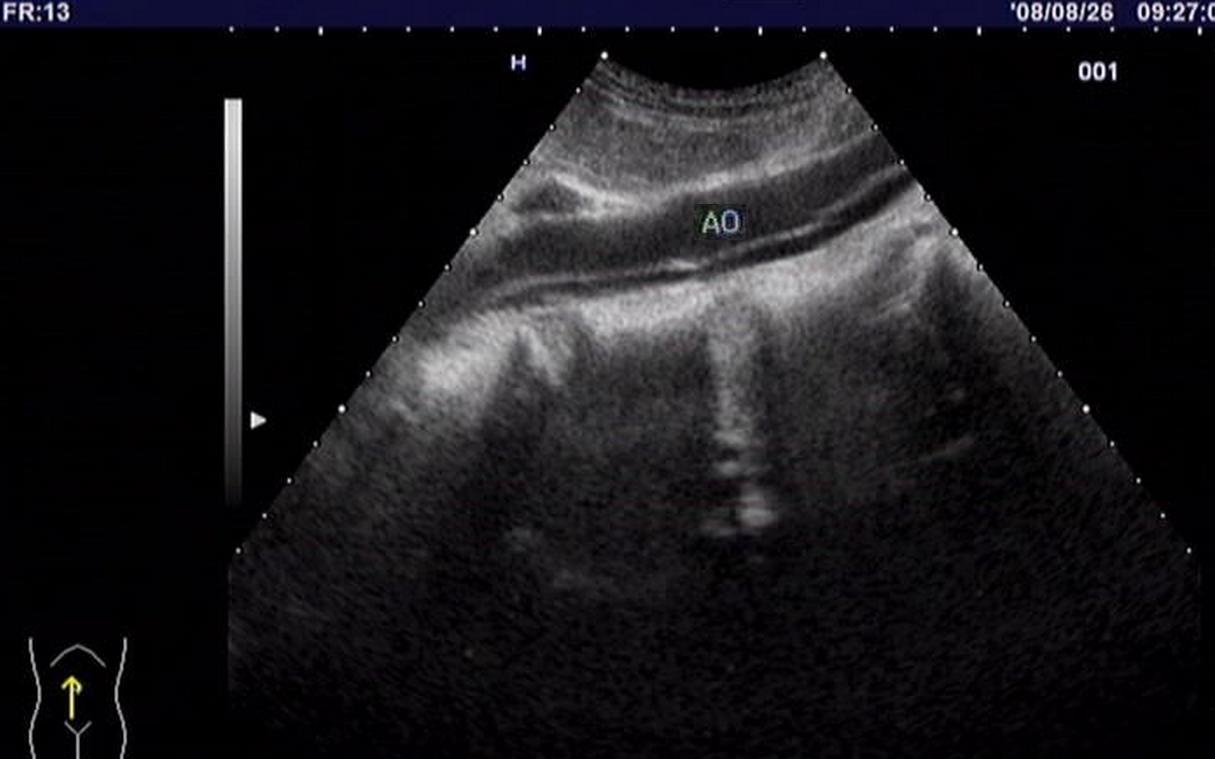

超声影像下的主动脉夹层:

图2:腹主动脉夹层(矢状面):AO为腹主动脉真腔,其下亮带为剥离的动脉内膜,稍窄的黑色条带为假腔。